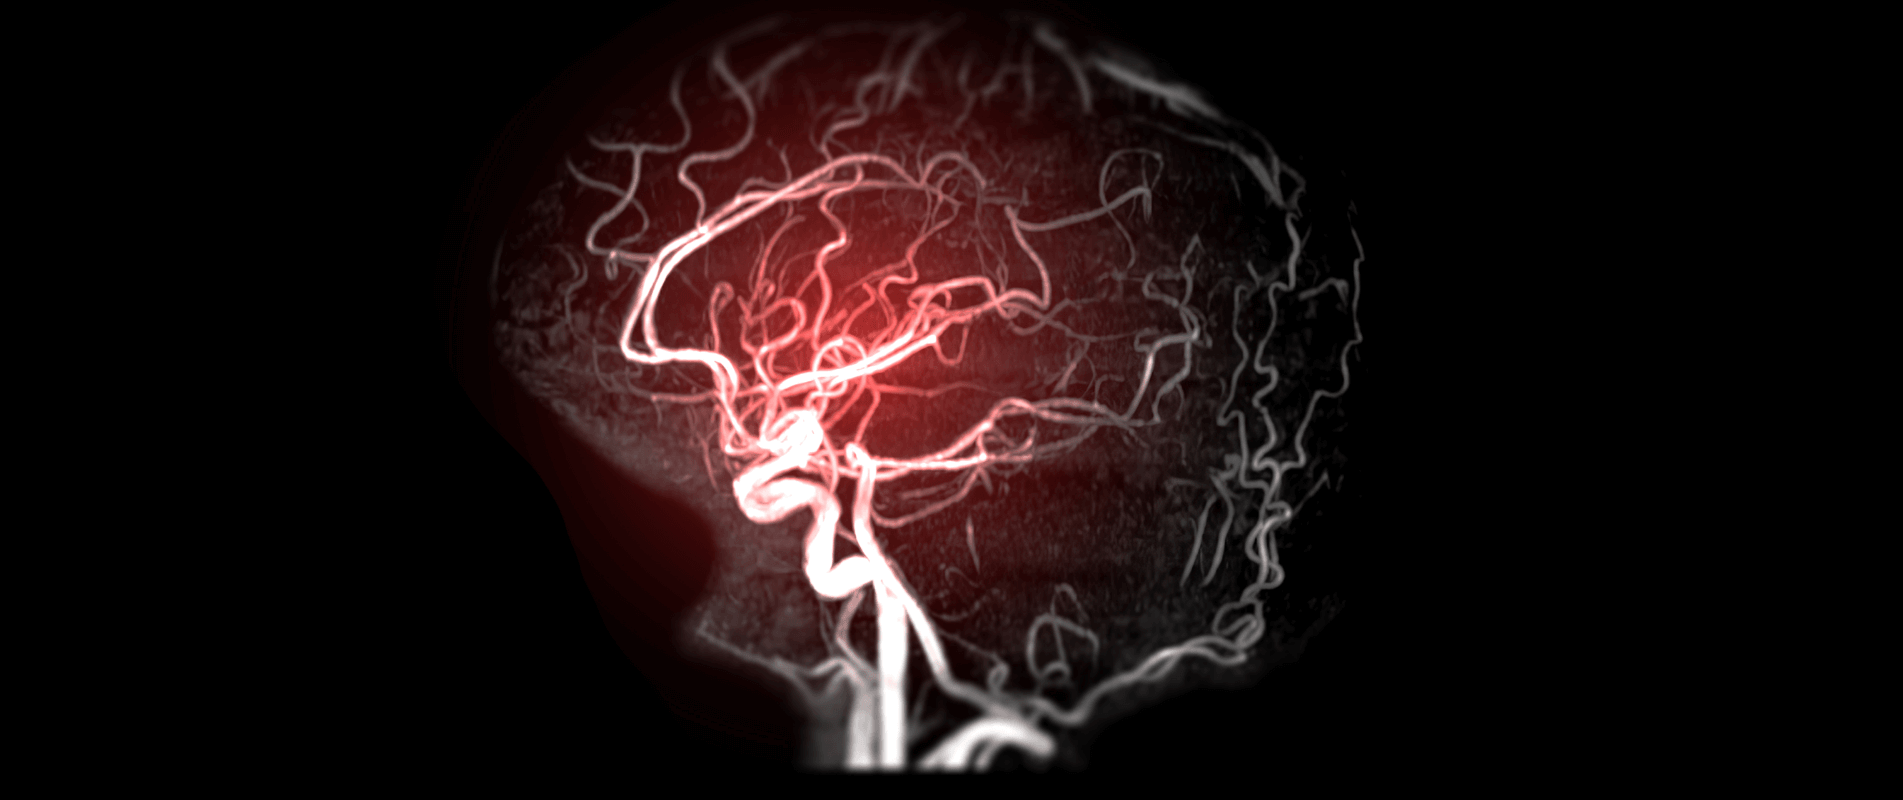

AVC-ul poate fi de două feluri:

- ischemic (adică obstrucția unui vas cerebral);

- hemoragic (presupune ruperea unui vas cerebral).